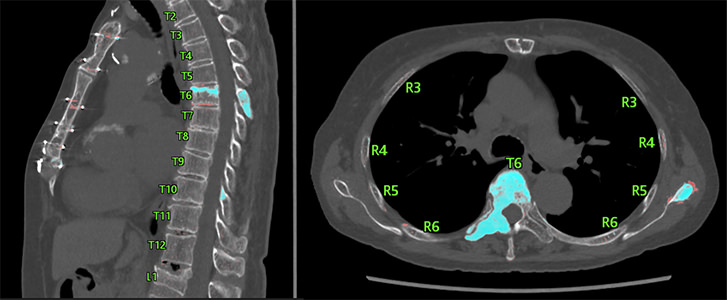

過去と現在の画像を重ね合わせた画像「Fusion画像」で骨の経時変化を強調して表示する「骨領域の経時差分表示」システム(赤、青の領域が差分)

京都大学とキヤノンは、独自のアルゴリズム開発や画像処理の工夫などを重ね、撮影条件が異なる画像でも、骨の経時変化に特化した差分画像を生成する位置合わせ技術を開発しました。加えて、差分画像に脊椎や肋骨位置を表示するラベリング技術も実現。これらの技術により、病変の存在する部位の確認が容易になりました。実際にこのシステムを用いたことで、読影時間が3分の1に短縮されたケースが報告されています。

脊椎・肋骨のラベリング